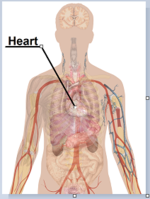

File:Tuberculosis symptoms.svg

| DescriptionTuberculosis symptoms.svg |

English: Main symptoms of different variants and stages of tuberculosis (See Wikipedia:Tuberculosis), with many symptoms overlapping with other variants, while others are more (but not entirely) specific for certain variants. Multiple variants may be present simultaneously.

Pulmonary tuberculosis symptoms

-

Extrapulmonary tuberculosis symptoms